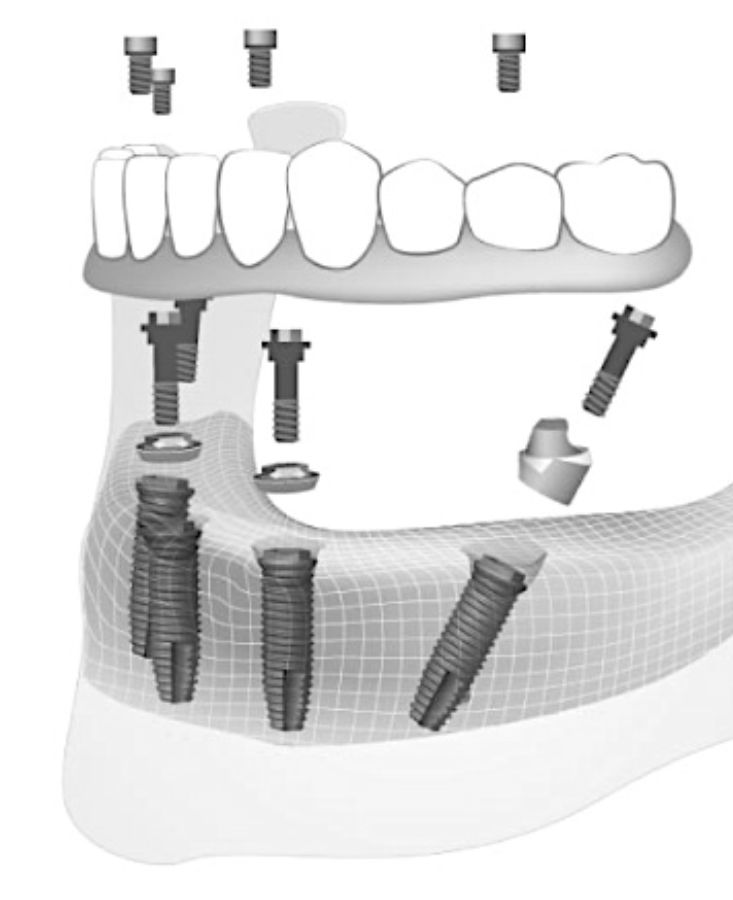

El protocolo All-on-4 consiste en la colocación de cuatro implantes dentales por arcada, y realizar una carga inmediata (dientes fijos sobre los implantes colocados  la primera semana tras colocar los implantes).

Los implantes  estarán estratégicamente distribuidos para maximizar el soporte óseo disponible:

• Dos implantes rectos en la parte anterior del maxilar o la mandíbula.

• Dos implantes angulados en la parte posterior, a aproximadamente 30°-45°, para evitar zonas con poco hueso y mejorar la estabilidad.

Esta disposición permite soportar una prótesis fija de arcada completa. La prótesis provisional suele incluir 10 dientes y permite una función masticatoria básica con dieta blanda; la definitiva, con hasta 12 dientes, se coloca tras 3 meses y no incluye los molares más distales​.